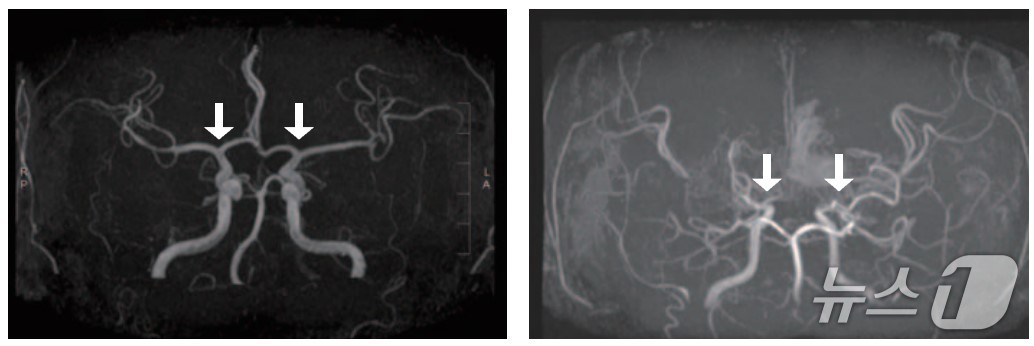

(왼쪽부터)정상 및 모야모야병 환자의 뇌혈관.(서울대병원 제공) |

모야모야병은 뇌로 혈액을 공급하는 혈관이 원인 없이 점차 좁아지는 만성 진행성 뇌혈관질환이다. 10세 전후 소아와 40세 전후 성인에서 주로 발병하며, 부작용으로는 뇌혈관이 막히거나 파열되는 허혈성·출혈성 뇌졸중이 있다.